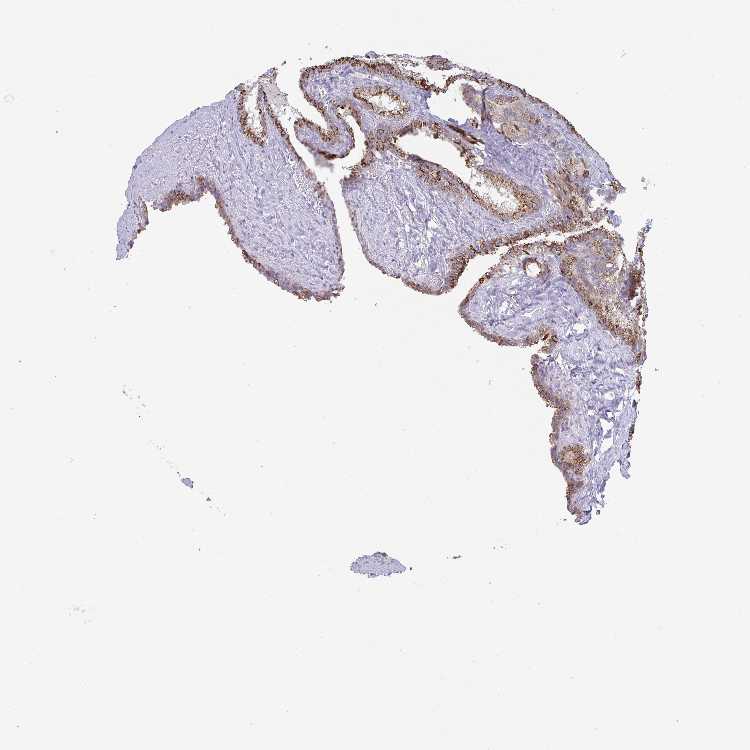

SEMINAL VESICLE - Antibody stainingi

Antibody staining in the annotated cell types in the current human tissue is reported as not detected, low, medium, or high, based on conventional immunohistochemistry profiling in selected tissues. This score is based on the combination of the staining intensity and fraction of stained cells.

Each image is clickable and will lead to virtual microscopy that enables deeper exploration of all samples and also displays staining intensity scores, fraction scores and subcellular localization as well as patient and tissue information for each sample.

Antibody HPA054829

Glandular cells Medium